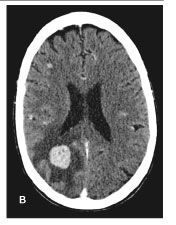

Figure 2. Abdominal ultrasonogram showing a mass (marked area) in the left lobe of the liver in an HIV/hepatitis C virus-coinfected man with hepatocellular carcinoma.

Since the beginning of the HAART era in 1996, there has been a noticeable increase in HCC among HIV-infected persons who are coinfected with hepatitis C virus (HCV) or hepatitis B virus (HBV) (Figure 2).59,60 Rosenthal and colleagues,61 in a French survey of causes of liver-related death in HIV-positive persons, demonstrated an increase in liver-related mortality due to HCC from 4.7% in 1995, to 11% in 1997, to 25% in 2001. Several cancer registry studies comparing HIV-positive with HIV-negative persons with malignancies have recently demonstrated a 4- to 30-fold increased risk of HCC among HIV-positive persons.5,6,62 In a large prospective cohort of 63,000 HIV-positive persons throughout the United States, HCC developed in 49 of the patients from 1992 to 2002.5 This was 4.5 times the rate expected in the general population. Galceran and colleagues6 found a 29-fold increase in HCC among a cohort of Spanish HIV-positive persons.

The increased incidence of HCC among HIV-positive persons can be attributed to several factors, including more rapid progression to cirrhosis in HIV-positive persons coinfected with HBV or HCV, increased survival of HIV/HCV- and HIV/ HBV-coinfected persons in the HAART era, and antiretroviral therapy-induced progression of underlying liver disease.61,63-67